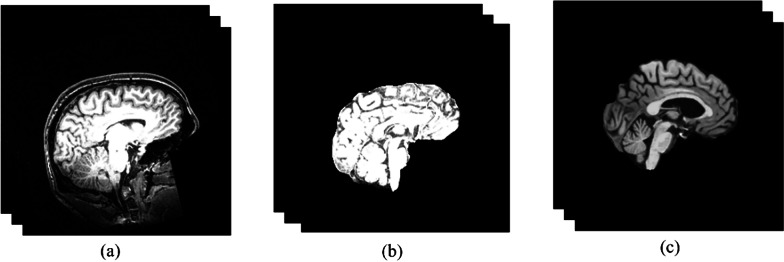

本研究利用脑磁共振成像图像研究了健康人的脑年龄与实际年龄之间的相关性,旨在确定阿尔茨海默氏症等神经退行性疾病的潜在生物标志物。为此,我们提出了一种新颖的基于注意力的 ResNet 方法--3D-Attention-Resent-SVR,通过计算脑年龄差距(BAG)来准确估计脑年龄并区分认知正常(CN)和阿尔茨海默病(AD)患者。与通常依赖单一数据集的传统方法不同,我们的方法采用四个数据集进行训练和测试,从而解决了潜在的偏差问题。结果表明,该模型在估算脑年龄差距时的平均绝对误差(MAE)为 2.05。此外,通过在三个数据集上进行训练并在另一个数据集上进行测试,该模型的通用性也得到了展示,其平均绝对误差为 2.4。此外,利用 BAG 作为唯一的生物标志物,我们的方法在 ADNI 数据集上检测阿尔茨海默病时达到了 92% 的准确率和 0.87 的 AUC。这些发现凸显了我们的方法在协助早期检测和疾病监测方面的潜力,同时强调了 BAG 与 AD 之间的强相关性。

This study investigates the correlation between brain age and chronological age in healthy individuals using brain MRI images, aiming to identify potential biomarkers for neurodegenerative diseases like Alzheimer's. To achieve this, a novel attention-based ResNet method, 3D-Attention-Resent-SVR, is proposed to accurately estimate brain age and distinguish between Cognitively Normal (CN) and Alzheimer's disease (AD) individuals by computing the brain age gap (BAG). Unlike conventional methods, which often rely on single datasets, our approach addresses potential biases by employing four datasets for training and testing. The results, based on a combined dataset from four public sources comprising 3844 data points, demonstrate the model's efficacy with a mean absolute error (MAE) of 2.05 for brain age gap estimation. Moreover, the model's generalizability is showcased by training on three datasets and testing on a separate one, yielding a remarkable MAE of 2.4. Furthermore, leveraging BAG as the sole biomarker, our method achieves an accuracy of 92% and an AUC of 0.87 in Alzheimer's disease detection on the ADNI dataset. These findings underscore the potential of our approach in assisting with early detection and disease monitoring, emphasizing the strong correlation between BAG and AD.